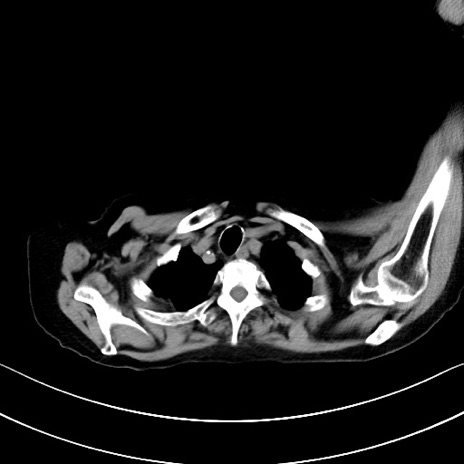

横断像

他院CT